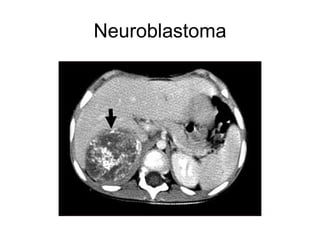

Neoplasias Neurogénicas 75% en mediastino posterior Benignas 80%. Nervios periféricos: Schawnoma, neurofibroma. Ganglios autónomos. Ganglioneuroma, neuroblastoma, ganglioneuroblastoma En relación con la edad Neuroblastoma < 3 años Ganglioneuroblastoma 3 – 10 años. Ganglioneuroma > 10 años.

Neuroblastoma